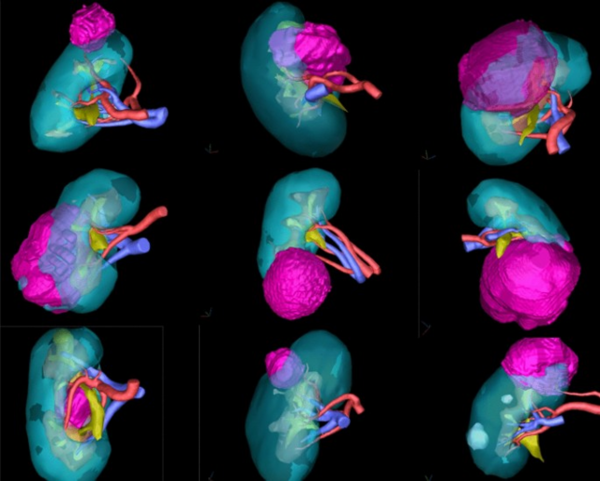

(局部腎癌切除手術圖解)

中大醫院引入最新3D 醫學影像重建技術 , 可以準確分析腎臟血管分布 , 腫瘤位置以及周邊結構, 提高手術成效。